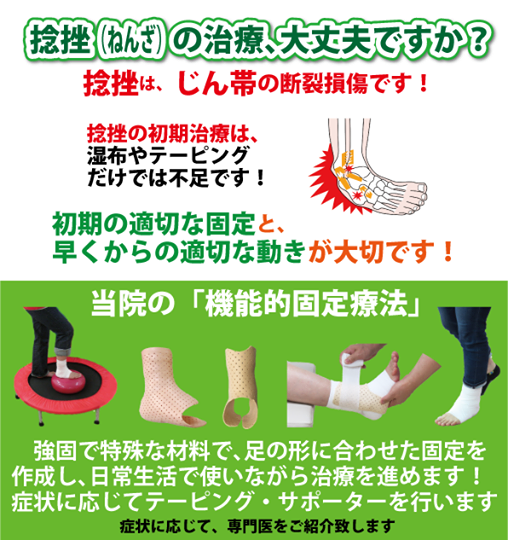

湿布の効果は何時間?短い時間でも効果はある?薬剤師が湿布 捻挫した場合にサポーターはいつまで着ける?その期間とは!? 足関節(足首)捻挫には湿布?アイシング?テーピング?捻挫 捻挫を早く治したいときは?捻挫の対処方法と処置の捻挫によくある症状 温感湿布と冷間湿布のどちらを使えばいいのか分からない 応急処置はどう対処したらいいのか知りたい 捻挫がクセになってしまいそうで不安 捻挫を未然に予防する方法を知っておその前に、説明を分かりやすく するために、 足首捻挫の分類から説明します。 足首を捻った(ひねった)方向による分類 一般的には大きく分けて、2つのタイプの捻挫があります。 一般的な捻挫の分類 1.内返し捻挫(内反強制) 足を内側に捻る 2.

捻挫(ねんざ)したらどうする? 捻挫(ねんざ)は、とくに足首や指に起こりやすく、関節をひねって痛めてしまうことで起こります。 靭帯の損傷などが考えれらる場合は、整形外科での治療が必要です。 目立った腫れやひどい痛みといった症状がなければセルフケアで様子をみてもよいでしょう。 捻挫(ねんざ)直後の応急処置や、その後の手当についても · 特に応急処置の際、捻挫の患部に温湿布を貼ることは禁物です。 軽度の捻挫でも、しばらくは飲酒、湯船に浸かる入浴、運動などは避けましょう。 また、立ち仕事も数日は控え、医師の指示に従いながら再開するようにしましょう。2601 · 足首の外側が痛む場合は、 湿布を半分に折って中心部分に切れ込み をいれましょう。

· 足首の捻挫は、湿布を貼ってほっておけば治るものではなく、治療の難しさは、骨折以上に難しいです。 ほかの病院へ行くべきではないかなと思います。 そのときに、足首の捻挫に詳しい先生を捜すべきだと思います。 · 足首の捻挫に湿布は必要ですか? 無事に内出血していれば 患部は腫れていますので 浸出液も必要ですが 腫れを引かせてからの足首の固定が 1番大事ですから湿布を使って腫れを取ります。 腫れが引いて来たならば 冷やすのは止めて温湿布に切り替えます。 · 効果的な湿布の貼り方 捻挫や打撲などで熱をともなうときは冷湿布を使います。 冷湿布は冷蔵庫で保存しておくと、より効果的です。 湿布の形は2タイプあり、急性の痛みにはパップ剤、慢性的な痛みにはテープ剤が良いとされています。

捻挫で湿布を使用する期間はいつまで? 冷やす温めるが大切です! スポンサーリンク 捻挫というのは靭帯が損傷する怪我です。 靭帯を損傷すると痛みだけでなく、腫れや内出血を伴いこともあります。 きちんと処置することによって早期完治だけでなく再発を防ぐことや癖になることを防ぎます。 この場合に湿布を使用する期間というのはいつまででしょうか

11 13 捻挫をこじらせないためには 初期の適切な治療が大切です 柔道整復師 西原清 マイベストプロ大分